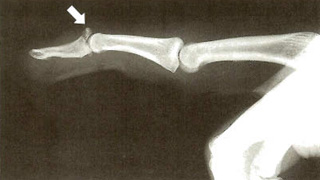

医師が指を見て症状について話し、脱臼の疑いがある場合でも、骨折や骨折を除外するために X 線検査が必要になる場合があります。

指が脱臼すると、骨が結合しなくなり、関節との位置がずれます。脱臼を経験する最も一般的な関節は、近位指節間 (PIP) 関節です。ここは指の真ん中の関節です。

- 指の骨が片側に突き出ているなど、ずれているように見える